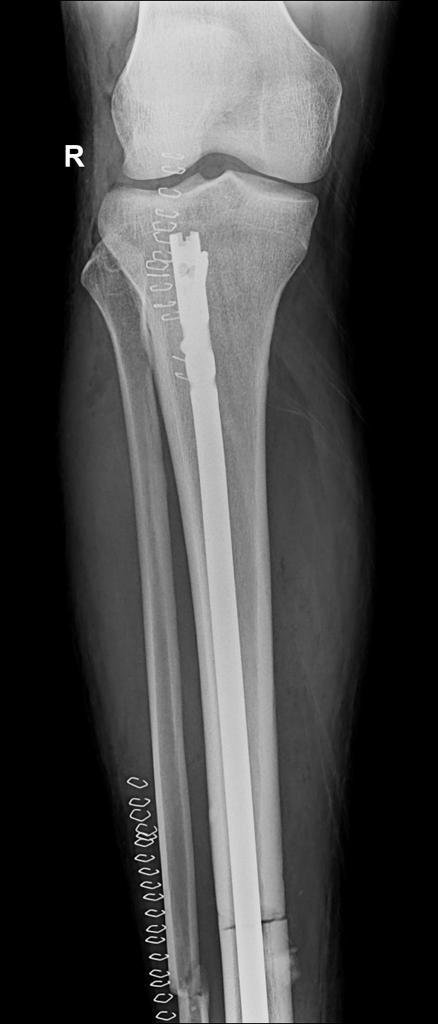

Nyuma y’umunsi umwe umunyezamu Kimenyi Yves wa AS Kigali agize imvune ikomeye cyane amagufwa y’agatsitsino agatandukana, ubu yamaze kubagwa.

Amakuru meza ahari ni uko Kimenyi Yves yabazwe neza n’umuganga kabuhariwe mu kunga amagufa ukorera mu bitaro by’inkuru nziza biri Gikondo.

Nk’uko byatangajwe na AS Kigali, mu mafoto bashyize hanze, ubu igufwa ryatandukanye uyu muganga yamaze gushyiramo insimburangingo izatuma igufwa ryongera guhura neza.